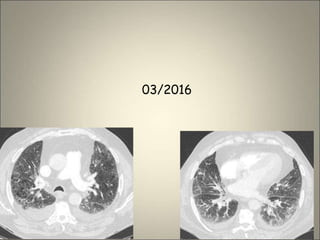

Œdème interstitiel et alvéolaire sur BPCO

2006 8/2015 01/2016

03/2016

Œdème interstitiel etalvéolaire sur BPCO 2006 8/2015 01/2016